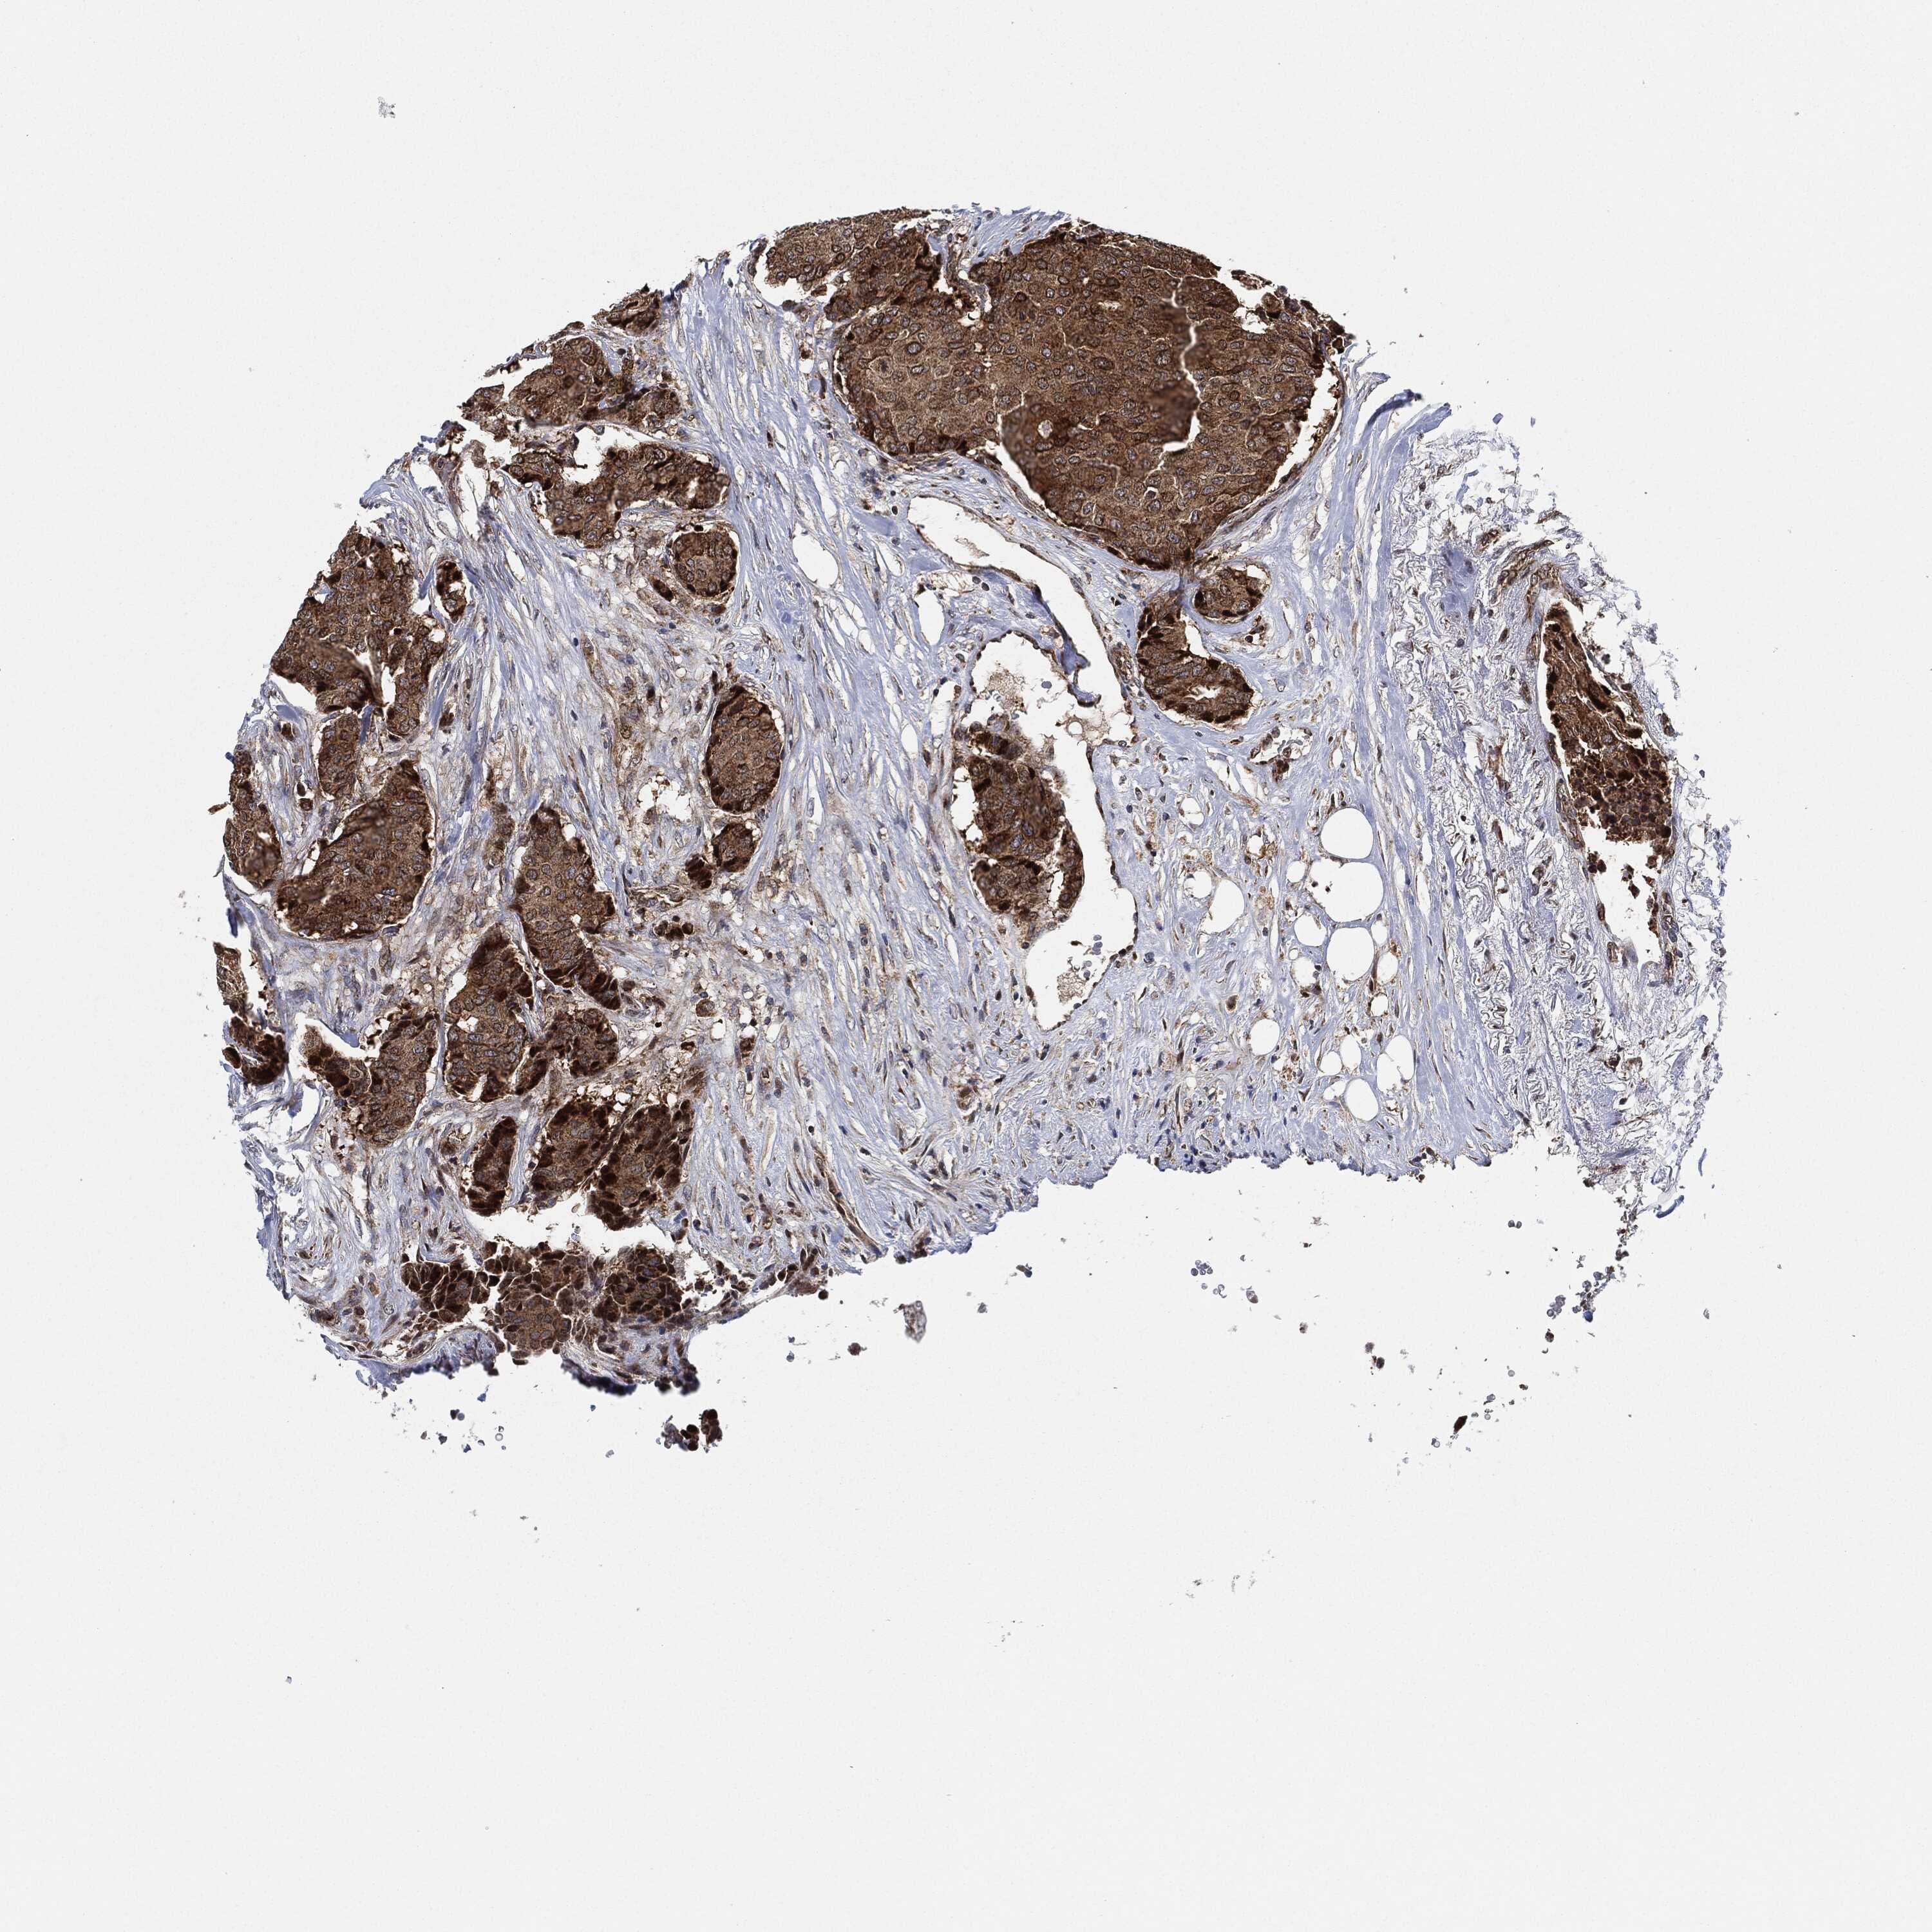

CANCER BREAST CANCER Show tissue menu

BRCA TCGA BRCA VALIDATION PROTEIN EXPRESSION